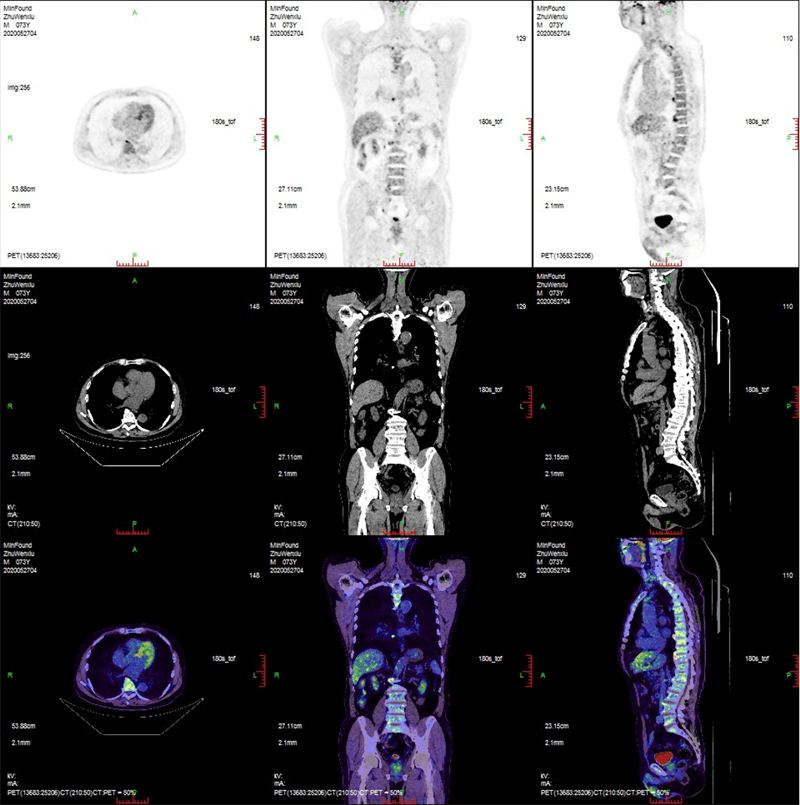

臨床畫廊